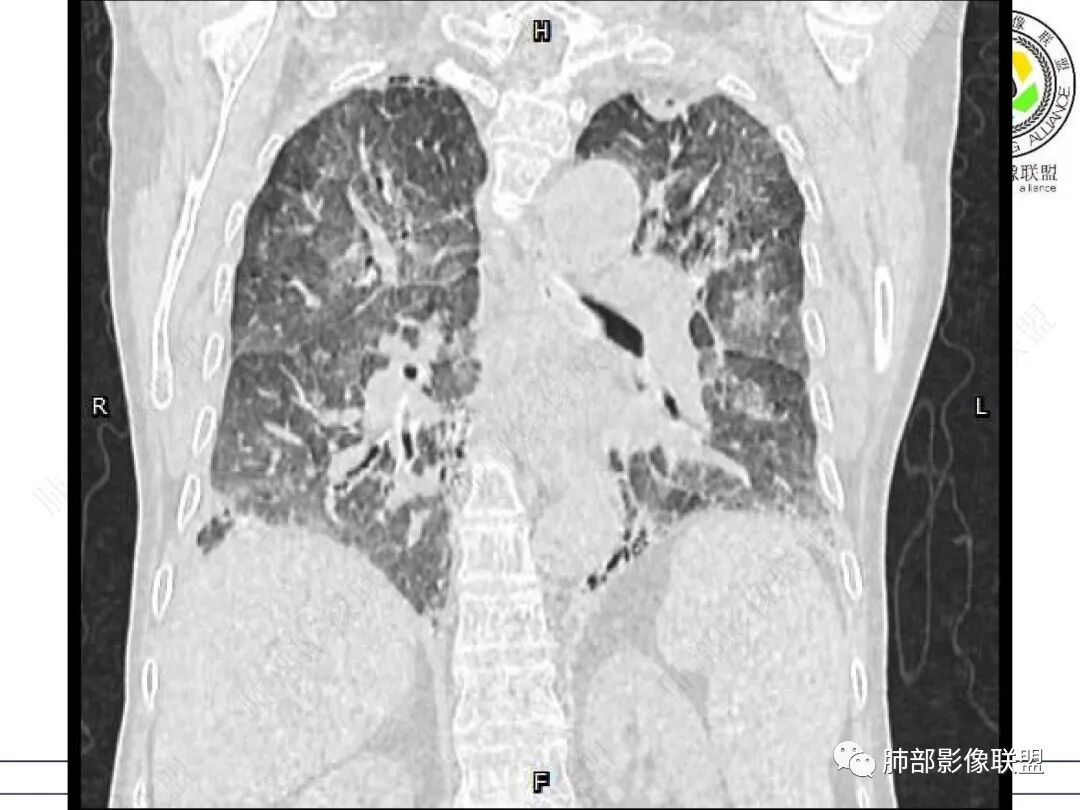

两肺叶后肋膈角区见多发蜂窝状结构破坏表现,双肺叶小叶间隔增厚,左肺上叶后段及舌段和右肺中叶胸膜炎性肉芽肿特点,双侧胸腔少量积液,有类风湿性关节炎治疗史,结缔组织相关性间质性肺病。

发热,有类风湿性关节炎、糖尿病基础病,长期口服激素及免疫抑制剂,双肺多发磨玻璃影及小叶间隔增厚,蜂窝影,支气管扩张考虑非特异性间质性肺炎存在,左肺上叶不规则结节影,周围长毛刺局部肺气肿,考虑慢性炎症,结合pct及crp升高考虑细菌感染,另真菌g升高考虑结合宿主因素,真菌感染需要积极排除。

老年,外阴溃疡加发热,感染指标明显有异常,血气分析,过度呼吸及低氧血症,宿主因素,糖尿病和激素,基础疾病RA。影像,双下肺体积有缩小,有蜂窝?双肺磨玻璃,多发结节,双侧胸水。树芽不明确。是否有旧片,这个患者有UIP背景,是否感染或者UIP急性加重,或者基础上合并肺栓塞及肺水肿?长期激素,没有提供CD4细胞亚群,存在2种情况,1,风湿病没有压制住,肺考虑CTD相关性间质改变,压制过猛,结合感染指标,奴卡是有可能的。激素加糖尿病,结核也带排,激素加磨玻璃加G实验阳性,PCP也带排,临床信息太少,进一步排查

老年女性,类风湿关节炎病史多年。发热。以两肺下叶为主弥漫磨玻璃及网格状透亮影,透亮度减低,局部小蜂窝状改变;两肺胸膜下散在几枚实性病灶;双侧胸腔积液。考虑RA-ILDNSIP

两下肺多发蜂窝状表现,双肺小叶间隔增厚,双肺磨玻璃影及部分炎性肉芽肿表现,双侧胸腔积液,有类风湿性关节炎治疗史,结缔组织相关性间质性肺病。患者C反应蛋白和降钙素原都高,是否合并细菌感染

女,71,外阴疼痛2周,发热1周。类风关、高血压、高血糖、卵巢囊肿、肠粘连、胆囊结石等病史及相关药物治疗史。胸部CT:两肺弥漫磨玻璃,血管束增粗,两下肺后肋膈角多发蜂窝,对称分布,双侧胸腔少量积液,纵隔窗心脏大血管影明显增宽。考虑混合性病变,CTD-ILD,并肺水肿?并PJP?。

老年女性,外阴溃疡伴发热,有类风、糖尿病病史,血象及炎症指标高,G试验升高;影像:磨玻璃密度(中央分布为主)胸膜下蜂窝状改变心影增大、两侧胸腔少量积液;小叶间隔增厚,结节;考虑:1.中央分布为主的GGO需考虑:肺水肿、出血、PJP、肺泡蛋白沉着症;2.胸膜下间质性改变蜂窝肺,需考虑UIP、CTD-ILD,综合:两元论:CTD-ILD奴卡,或肺水肿

双肺下叶多发蜂窝影,双肺小叶间隔增厚,双肺磨玻璃影,双侧胸腔积液,有类风湿性关节炎,考虑结缔组织相关性间质性肺病,合并感染

①影像表现复杂:较弥漫间质性改变,对称磨玻璃密度为主,小叶间隔增厚,有一定重力分布趋势,未见明显纤维化,气囊及蜂窝位于肺边缘,未见典型“月弓征”。心脏影增大,双侧胸腔积液。

这即可见于间质性肺病,也可见于真菌感染(如PJP)、病毒感染,类风湿,以及肺水肿等等。

一般而言,如存在磨玻璃密度影浑浊,有重力分布趋势,肺表面蜂窝影,胸腔积液等等,并不常见于单纯PJP,除非其他因素叠加。

患者存在肺水肿应当是合理的解释。其他旁证还有,心脏影增大,肾小球滤过率降低,双侧胸腔积液等等……

上肺斑片影、结节影,夹杂纤维条索影,边界清楚,新旧不等,胸膜牵拉明显等等,符合较典型继发性肺结核表现,但它却未必是此次就医主要责任病原体!